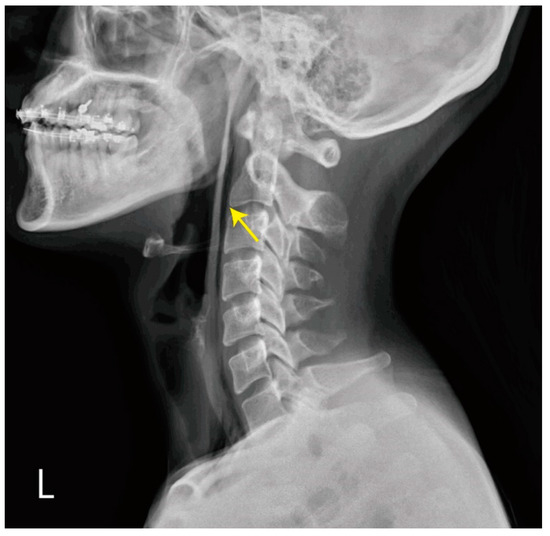

Point-of-Care Ultrasonography Helped to Rapidly Detect Pneumomediastinum in a Vomiting Female

2. Case Presentation